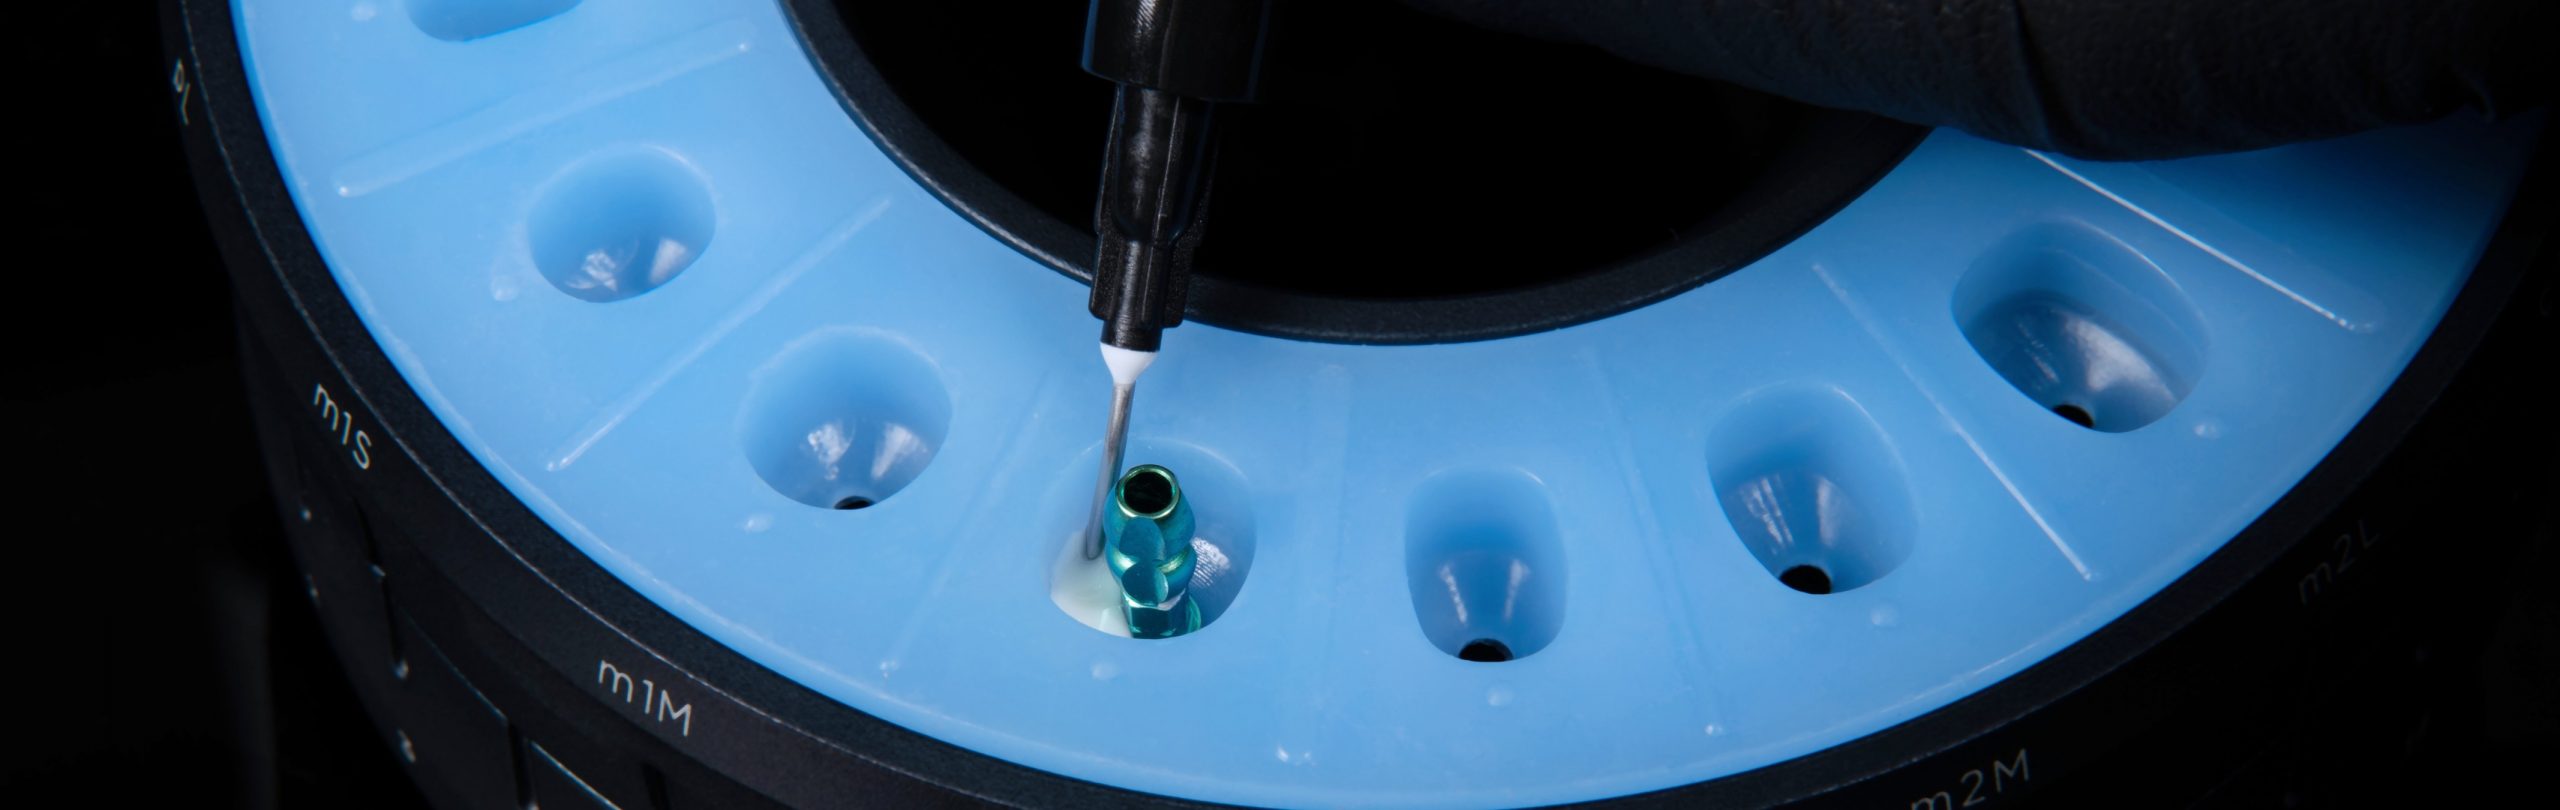

Pasul 5 – Procesul de duplicare a amprentei după fabricare

Asistentul instalează un stâlp de imprimare a stocului în același puț al matriței care a fost folosit pentru fabricarea bontului personalizat de vindecare (de exemplu, pS).

El / Ea introduce apoi materialul compozit adecvat în spațiul deschis și vindecă ușor cu unul sau mai multe trepte.

Apoi dezinstalează postul de imprimare duplicat creat și continuă cu lustruirea suprafeței compozite și dezinfectarea corespunzătoare.

Procesul de duplicare a amprentei după fabricare se poate face după programarea la consultație, sau la operație sau chiar înainte de etapa de amprentă, deoarece necesită doar aproximativ 4 minute pentru a fi finalizată.

Rotește inelul superior al matriței până când puțul de dublare este aliniat la insertul de conexiune protetică VPI dorit prezent la baza matriței.

Aplică un agent lubrifiant pe pereții interiori ai puțului de dublare.

Instalează bontul de vindecare personalizat modificat sau proteza temporară în puțul de duplicare.

Acest proces poate fi efectuat chiar înainte de instalarea finală a bontului de vindecare personalizat modificat sau a protezei temporare la implant (Preferabil); Sau chiar înainte de etapa de impresie.

Pasul 2 – Etapa de duplicare

Introdu material transparent de amprentă din silicon în spațiul liber disponibil și lăsați-l să se stabilească conform instrucțiunilor producătorului.

Pasul 3 – Etapa de duplicare

Dezinstalează bontul de vindecare personalizat modificat sau proteza temporară din puțul de dublare.

Instalează în puțul de dublare un post de imprimare adecvat.

Pasul 4 – Etapa de duplicare

Umple spațiul liber disponibil cu material compozit adecvat și fotopolimerizare într-unul sau mai multe trepte *.

Umple spațiul liber disponibil cu material compozit adecvat și fotopolimerizare într-unul sau mai multe trepte *.

Dezinstalează postarea de impresie duplicat generată din puțul de duplicare.

Postarea de afișare personalizată generată este acum duplicatul exact al bontului de vindecare personalizat modificat sau proteză temporară cel puțin la porțiunea lor sub-fuzionată.

Îndepărtează materialul de amprentă din silicon din puțul de dublare utilizând un clește de bumbac sau alt instrument adecvat.

* În cazul în care utilizezi un material de imprimare din silicon care nu este limpede (colorat), este recomandabil să umpli spațiul cu material compozit și întărire ușoară în trepte mici. Acest lucru va asigura întărirea adecvată a materialului compozit.